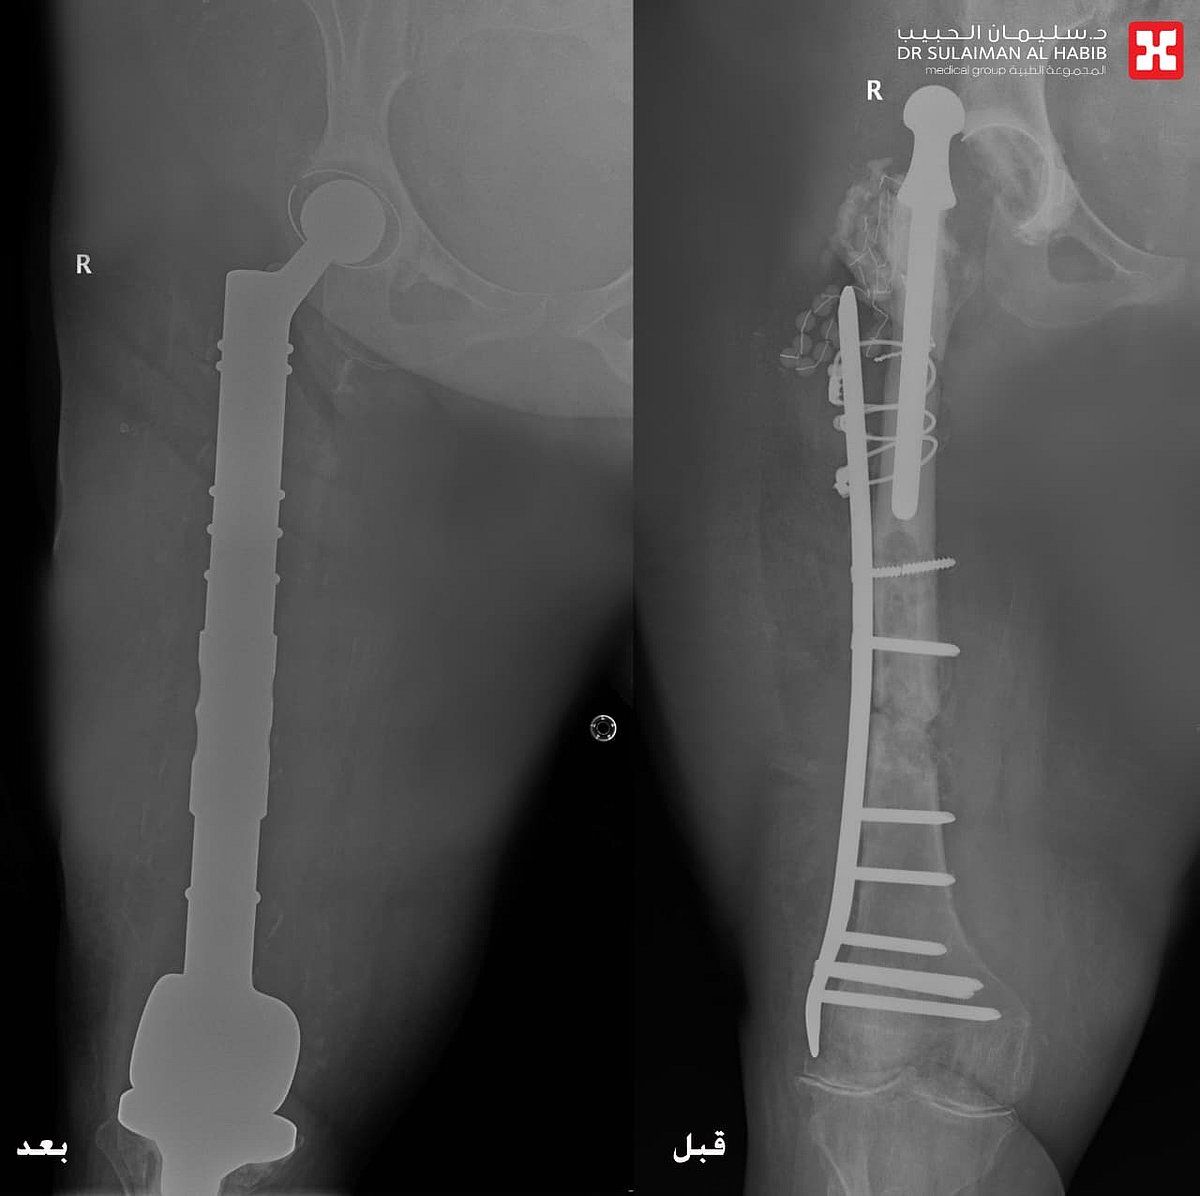

وقال د. "الرفاعي" الحاصل على الزمالة السويسرية، أن المراجعة جاءت إلى المستشفى بحالة صحية معقدة، إذ أظهرت الفحوصات الدقيقة وجود التهابات حادة ومزمنة وورم التهابي منتشر في مفصل الورك أدى لخروجه، وكذلك في عظمة الفخذ ومفصل الركبة، كما أنها كانت مصابة بمضاعفات عدم الحركة "تقرحات الفراش" وتصلب المفاصل والظهر، إضافة إلى سوء الحالة الصحية العامة.

وتابع د. "الرفاعي" قائلاً أن الفريق الطبي وضع خطة علاجية متكاملة مكونة من عدة مراحل، بدأت بإزالة المفصل القديم والورم الالتهابي الذي بلغ وزنه "20" كجم، ووضع أجهزة داخلية تحتوي على مضادات لعلاج الالتهابات، وبعد التخلص منها، جرى استبدال كلي لمفصلي الورك والركبة، وعظمة الفخذ، في تدخل جراحي معقد استمر لـ"5" ساعات، وتكللت جهود الفريق الطبي ولله الحمد بالنجاح التام، حيث نقلت المراجعة بحالة صحية مستقرة إلى غرفة التنويم، وتحسنت حالتها باضطراد مع العناية الطبية الحثيثة، وغادرت المستشفى بعد عدة أيام بحالة صحية ممتازة، ولاحقاً تخلصت من كافة الأعراض التي عانت منها طوال سنوات ما قبل العملية، حيث جاءت إلى المستشفى بعد عدة أسابيع مشياً على قدميها.